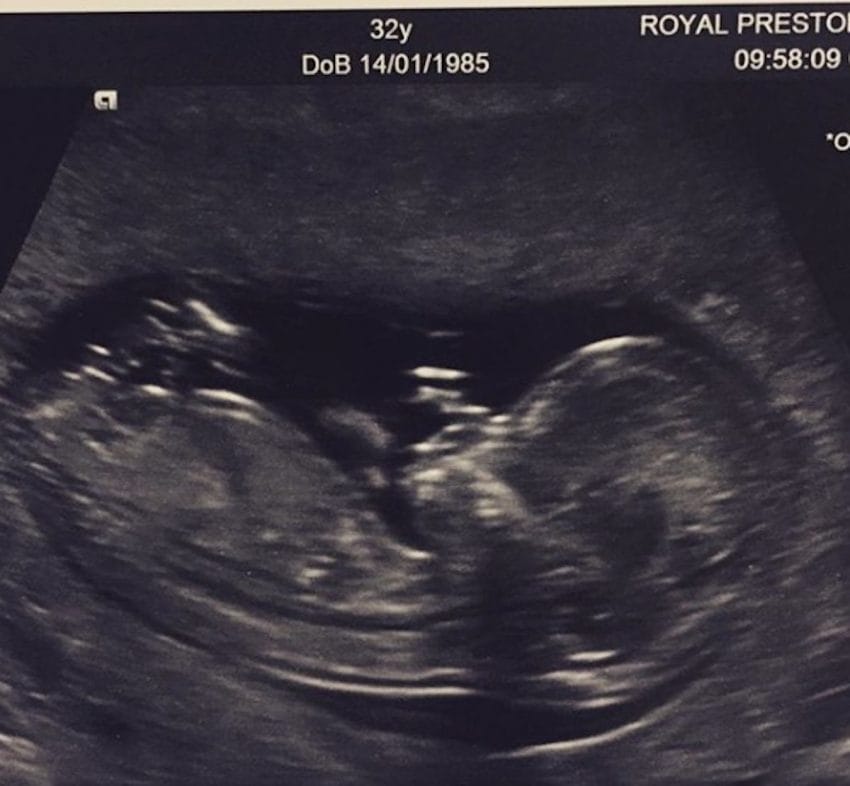

‘Ενα έμβρυο μπορεί να κάνει κάποιες ελαφρές κινήσεις (όπως είναι μια γροθιά) στις 12 εβδομάδες.

Ένα μωρό κάνει περισσότερα βήματα κατά τη διάρκεια του δεύτερου τριμήνου, όπως κάποιες κινήσεις πιπίλισμα ή την πρώτη κίνηση του εντέρου του!

Σε περίπου 20 έως 24 εβδομάδες, η μητέρα μπορεί να αισθάνεται “μια κίνηση” καθώς το χέρι του μωρού και τα αντανακλαστικά αρχίζουν να σχηματίζονται.

Κατά τη διάρκεια του τρίτου τριμήνου, οι κινήσεις ενός μωρού μπορεί να έχουν την αίσθηση ενός τρυπήματος ή ισχυρών ωθήσεων.